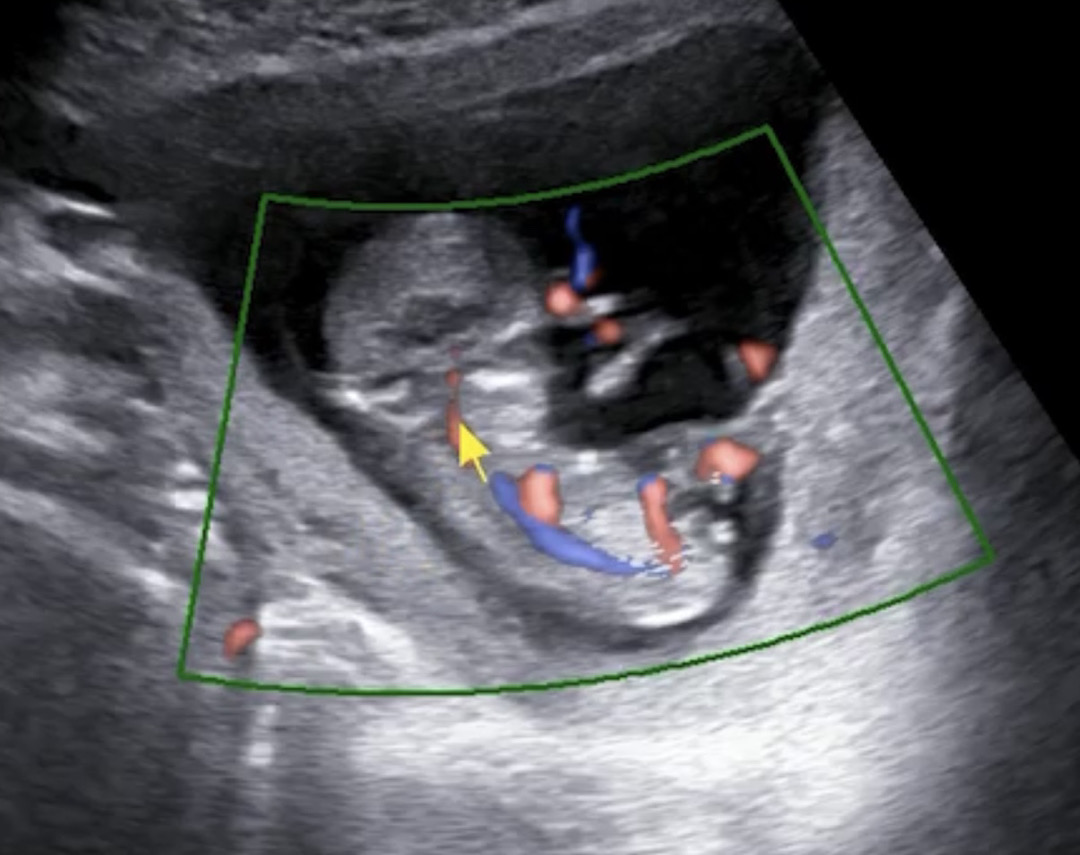

12주0일 각도법!

12주0일에 초음파 보고왔는데 각도법 고수님 계실까요 !! 한번 봐주세요 ㅠㅠ

엉덩이쪽에 흰색 두줄 있는데 그거 아닐까요 ?!